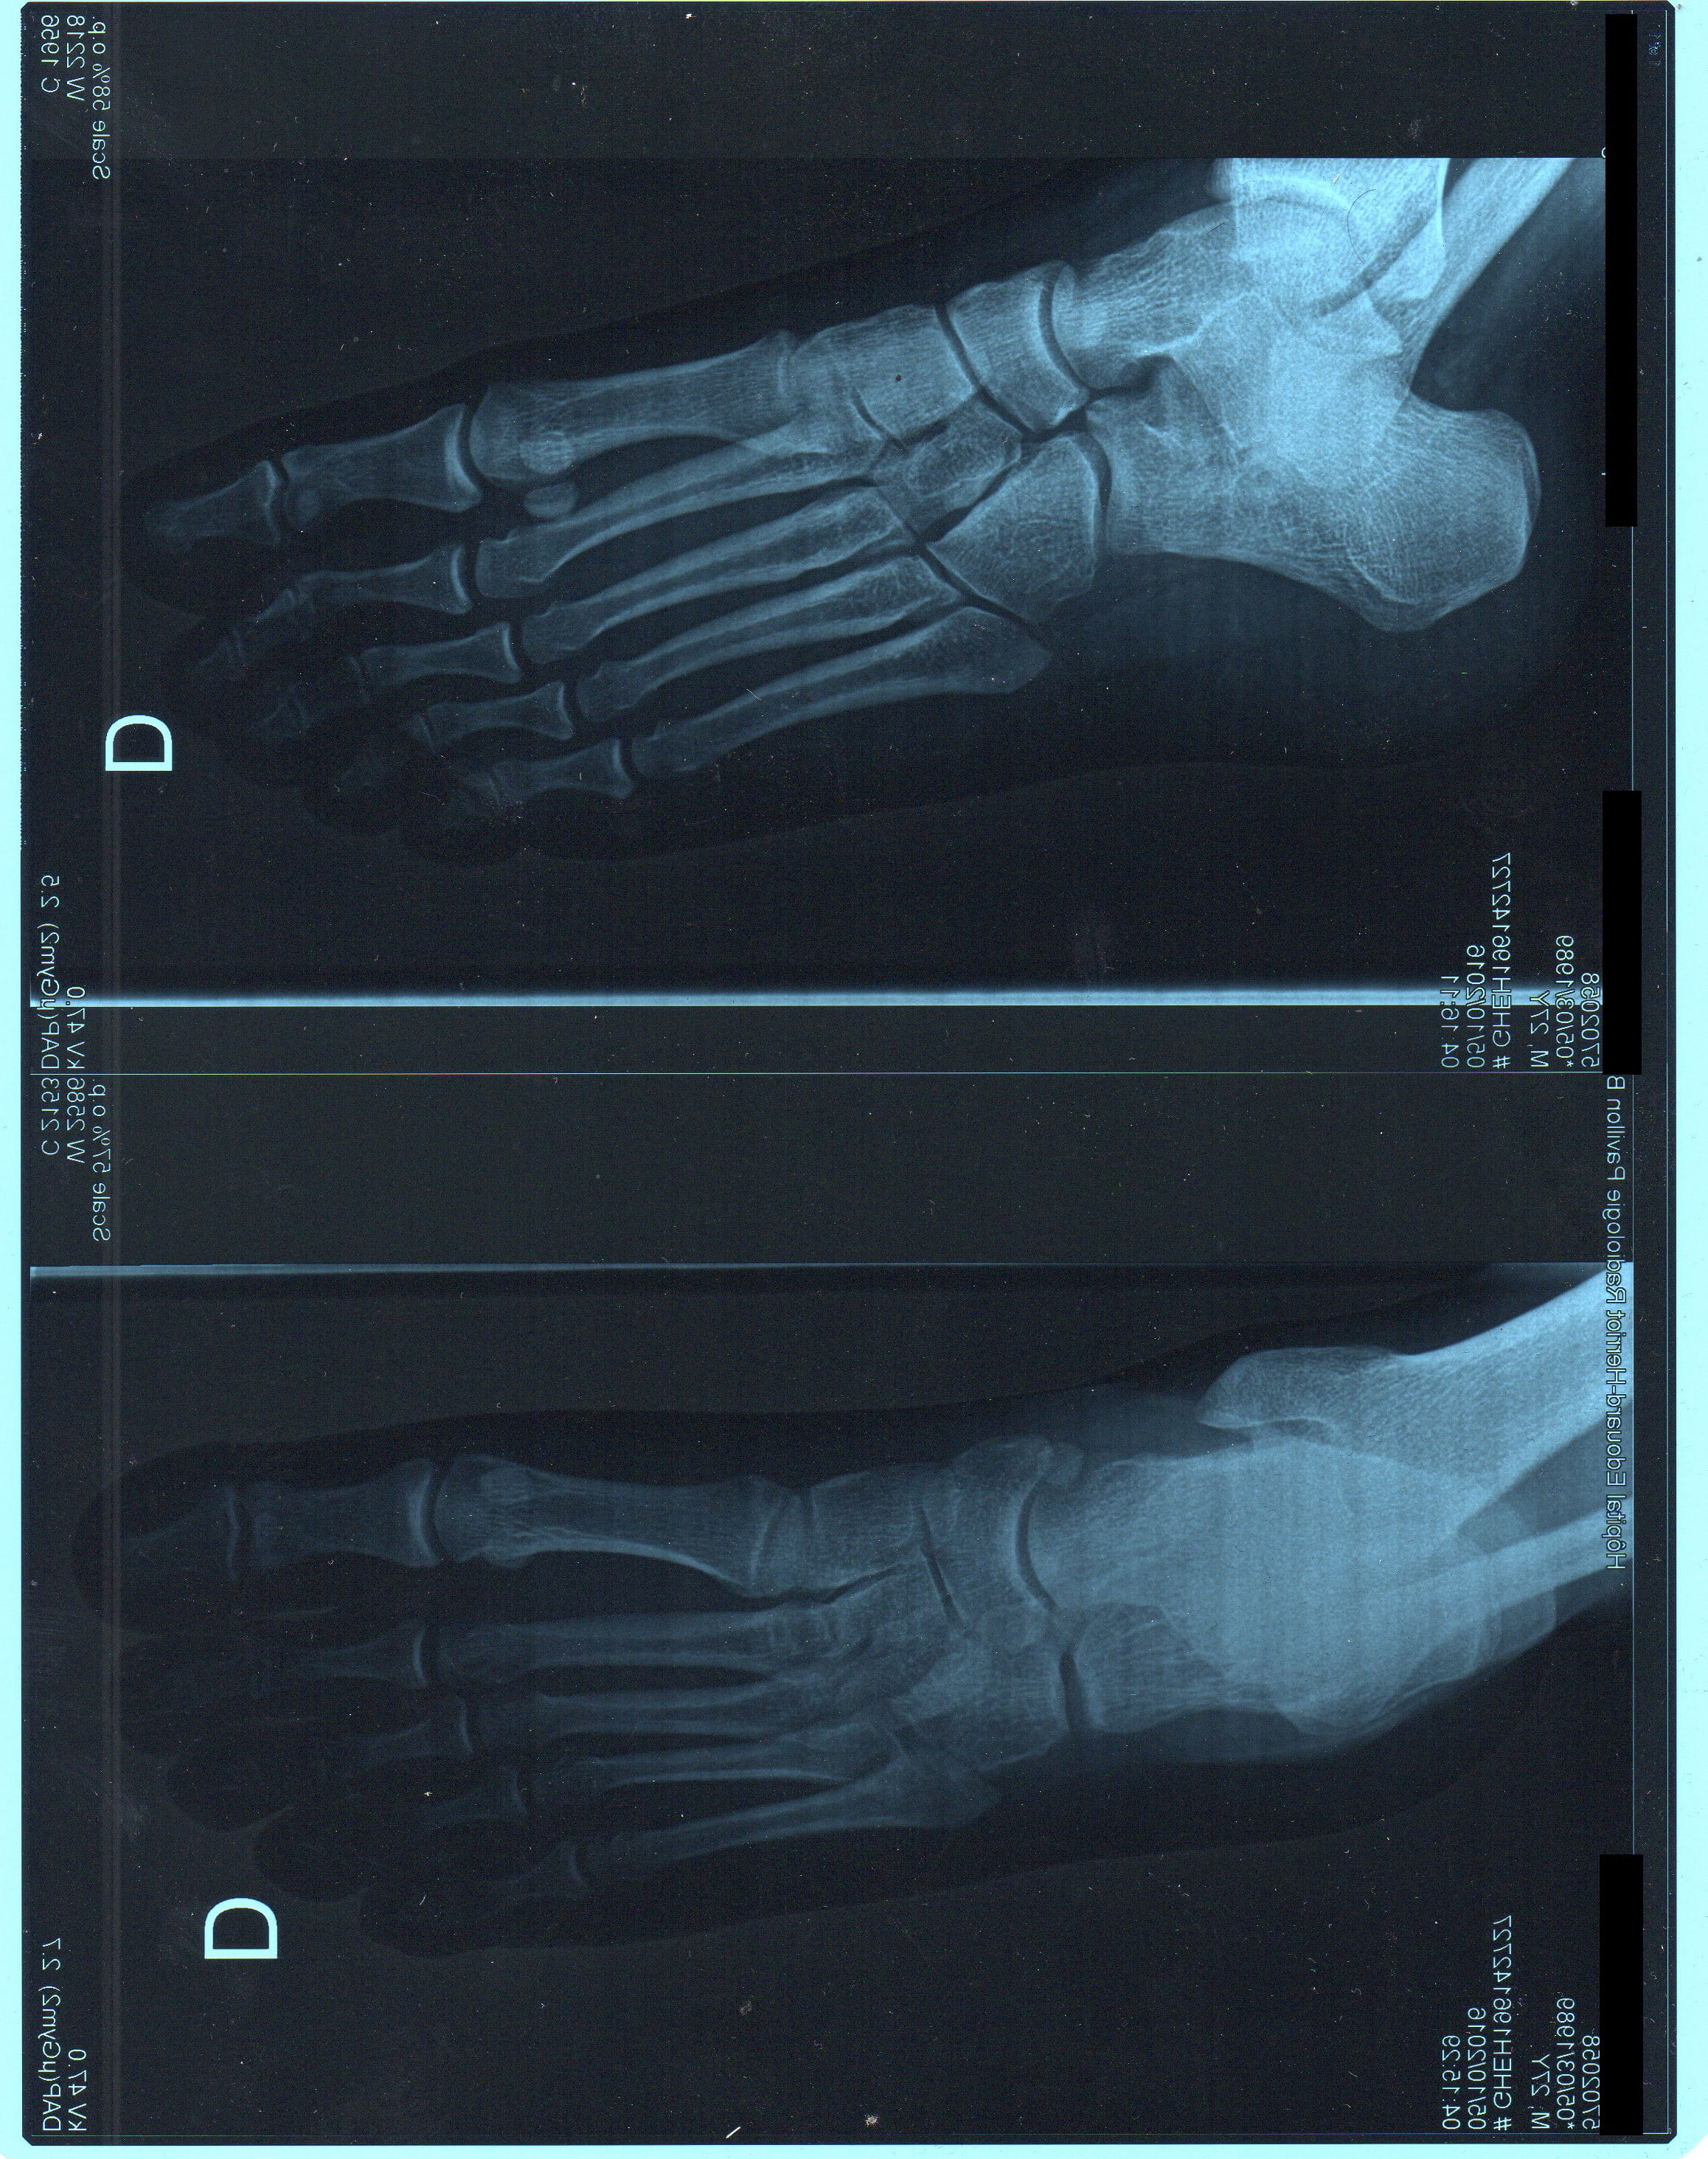

Je reviens du médecin et après étude de la radio de mon pied pour lui ce n’est pas une crise de goutte mais une infection du pied due à quelques coupures présentes entre mes orteils, un microbe s’y serait introduit. Mais il m’a dit à la fin que c’est son avis qu’il peut se tromper.

En voyant la radio de mon pied que j’ai mis en pièce jointe est-ce que selon vous le diagnostic est bon ? et est-ce que par hasard vous verriez des cristaux d’acide urique présents ?